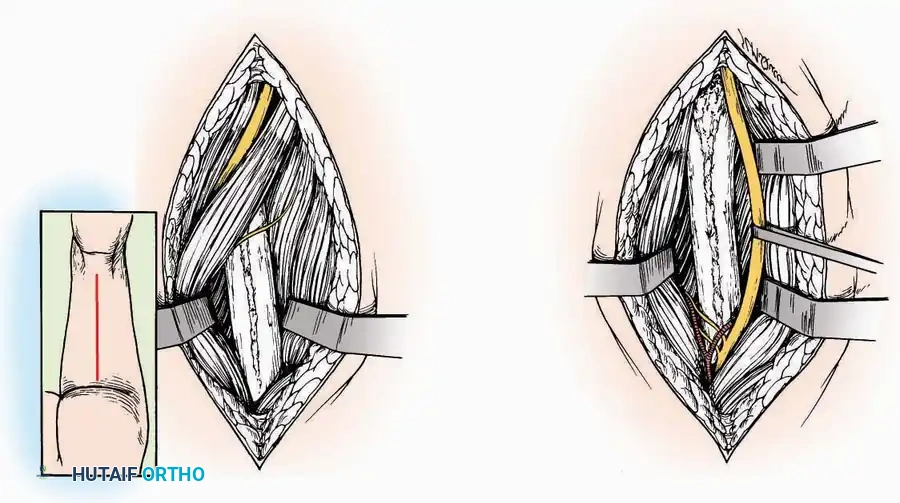

Anterolateral Approach

The anterolateral approach is widely considered the "universal incision" for the foot and ankle. It provides unparalleled access to the ankle joint, the talus, and the majority of the tarsal articulations, while safely avoiding the major anterior neurovascular bundle. The only tarsal joints inaccessible via this route are the naviculocuneiform joints (specifically the medial and intermediate).

Indications: Total talectomy, triple arthrodesis, ankle arthrodesis, and open reduction of complex talar neck fractures.

Surgical Technique:

* Incision: Begin over the anterolateral aspect of the leg, medial to the fibula and 5 cm proximal to the ankle joint line. Carry it distally over the joint, crossing the anterolateral aspect of the talar body and the calcaneocuboid joint, terminating at the base of the fourth metatarsal.

* Superficial Dissection: Incise the superficial fascia and the superior and inferior extensor retinacula down to the periosteum of the tibia and the ankle joint capsule.

* Vascular Ligation: This trajectory usually requires the identification and ligation of the anterolateral malleolar and lateral tarsal arteries.

* Nerve Protection: Retract the skin edges carefully. Identify and protect the intermediate dorsal cutaneous branches of the superficial peroneal nerve (SPN), which frequently cross the distal aspect of this incision.

* Muscle Management: Identify the origin of the extensor digitorum brevis (EDB) muscle on the lateral calcaneus. Divide it in the direction of its fibers, or detach its origin entirely and reflect it distally to expose the subtalar and calcaneocuboid joints.

* Deep Exposure: Retract the extensor digitorum longus (EDL) tendons, the dorsalis pedis artery, and the deep peroneal nerve (DPN) medially. Incise the anterior ankle capsule to expose the tibiotalar joint.

* Tarsal Exposure: Expose the talonavicular joint by dissecting deep to the extensor tendons and incising its capsule transversely. Continue laterally through the capsule of the calcaneocuboid joint. By excising the fat pad within the sinus tarsi (lateral and inferior to the talar neck), the posterior facet of the subtalar joint is brought into direct view.